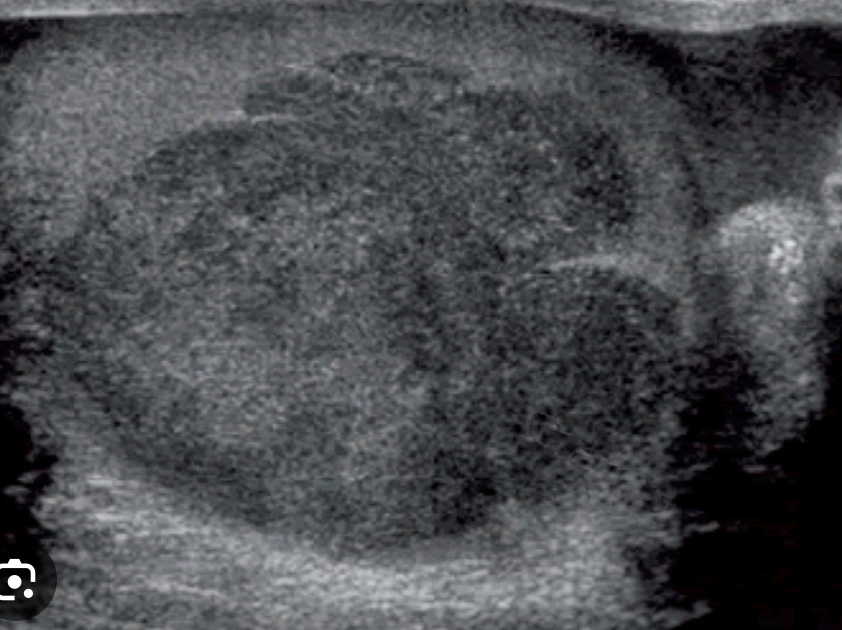

Dx imagen

A

USG escrotal

12

Q

como se ve al USG escrotal ??

Imagen heterogénea en el parénquima testicular

(el testÍculo normal es homogeneo)